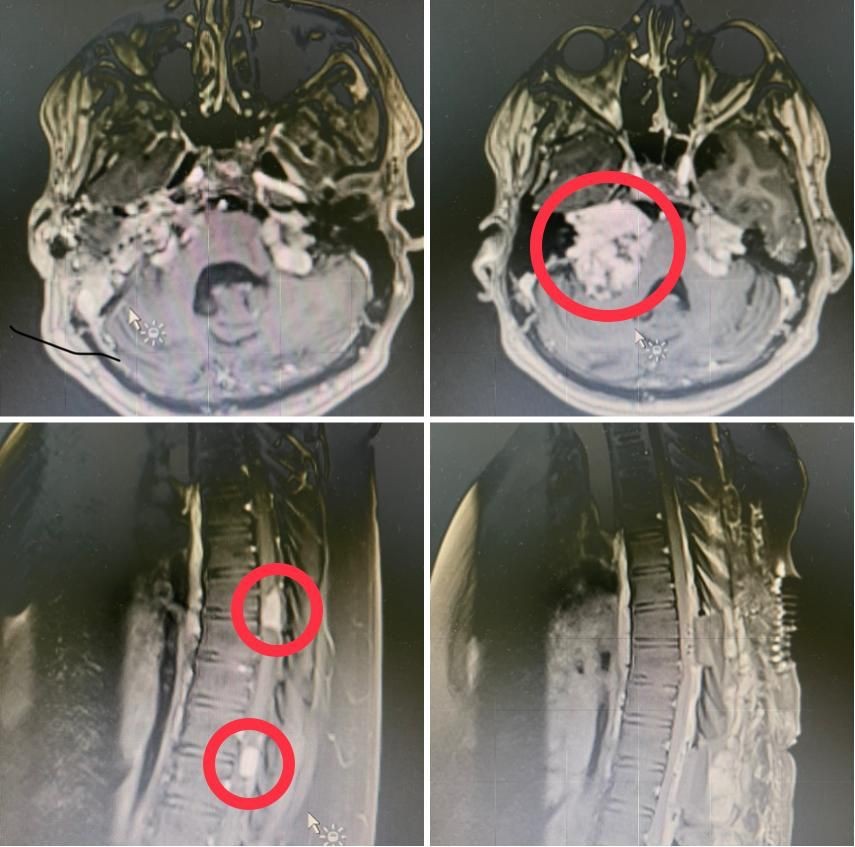

نجح فريق طبي تكاملي بمدينة الملك عبدالله الطبية بالعاصمة المقدسة عضو تجمع مكة المكرمة الصحي ممثلا بمركز العلوم العصبية من استئصال ورم ليفي عصبي ضخم في قاع الجمجمة ضاغطاً على جذع الدماغ بالإضافة إلى ورمين آخرين أحدهما سحائي والآخر ليفي ضاغطين على الحبل الشوكي لشاب في العقد الثاني في عمليه نادرة وعالية الخطورة.

واستقبلت المدينة الطبية المريض والذي كان يعاني من أورام ليفية عصبية متعددة ضاغطة على جذع المخ والنخاع الشوكي ، وقد تم محاولة علاجه عن طريق الإشعاع في أحد المستشفيات قبل عشر سنوات ومع ذلك لم ينجح العلاج الإشعاعي في التحكم في تطور المرض حيث استمرت الأورام بالزياده في الحجم مما أدى إلى عدم القدره على المشي بدون مساعدة.

في المرحله الأولى تم إزالة الورم الليفي العصبي الملاصق لجذع الدماغ تحت المراقبة العصبية وباستخدام جهاز الملاحة الجراحية والميكروسكوب الجراحي في عمليه استغرقت تسع ساعات حيث قام بإجراء التدخل الجراحي الدكتور محمد غازي عبده استشاري جراحة المخ والأعصاب والعمود الفقري والدكتور عصام صالح استشاري جراحات الأذن والدكتور سيد الأهل من تخدير الأعصاب والدكتور أسامة شمس من المراقبة العصبية الفسيولوجية حيث تحسنت حالة المريض بانتظار المرحلة الثانية.

حيث تم تحضير المريض لاحقا لعمل التدخل الجراحي الثاني للورمين الضاغطين على الحبل الشوكي في تدخل جراحي واحد وتحت المراقبة العصبية واستخدام الميكروسكوب الجراحي حيث استغرق التدخل الجراحي ست ساعات والتي أوضحت نتائجها وجود ورمين من نوعين مختلفين أحدهما سحائي والآخر ليفي

وتكللت ولله الحمد العمليات الجراحيه بالنجاح مع إزالة الأورام الضاغطة على الحبل الشوكي وجذع الدماغ مع تحسن قدرة المريض على المشي.